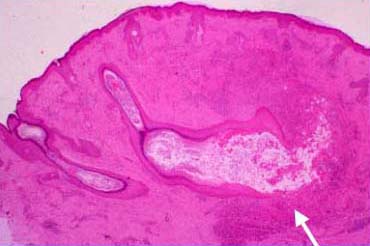

Atlas of skin histopathology

Acne vulgaris erythematous papule =العد الشائع